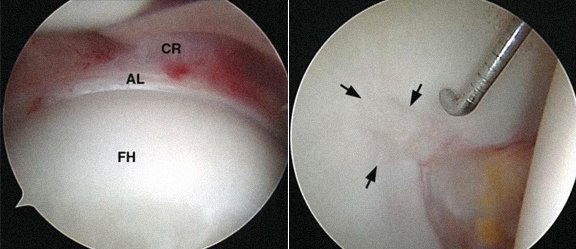

Deformidade óssea do rebordo acetabular (pincer)

Reparação e sutura de

lesão do labrum

Lesão da cartilagem articular, tratamento por desbridamento e microfracturas